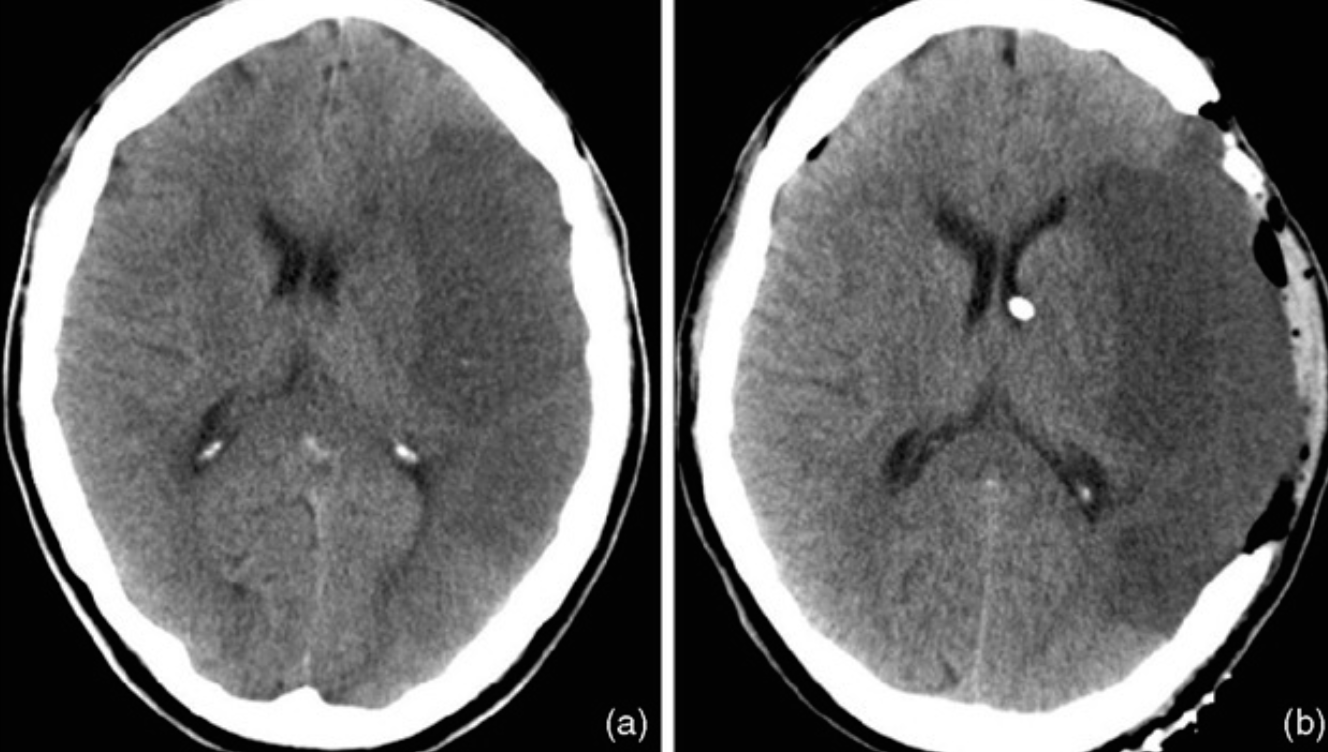

1. Describe 2 abnormal findings of the CT?

a. Left hypodense area occupy the left hemisphere (infarction)

b. Left carinotomy mark

2. Name vascular territory involved?

a. Middle cerebral artery